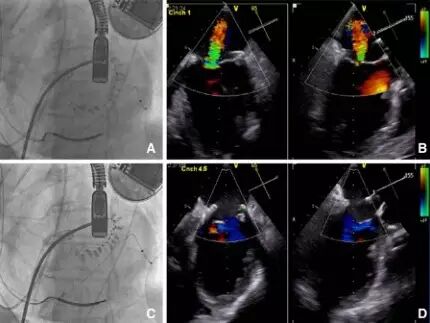

Clip通过24F的递送鞘管经过股静脉,通过房间隔穿刺,送入左心房,在导管室借助于经食道超声Clip直接置于二尖瓣返流柱上。抓住二尖瓣前后叶,返流量明显减少后可释放MitraClip装置。如果二尖瓣返流量减少不满意,可松开二尖瓣叶重新夹取直至满意为止。见图1

图1